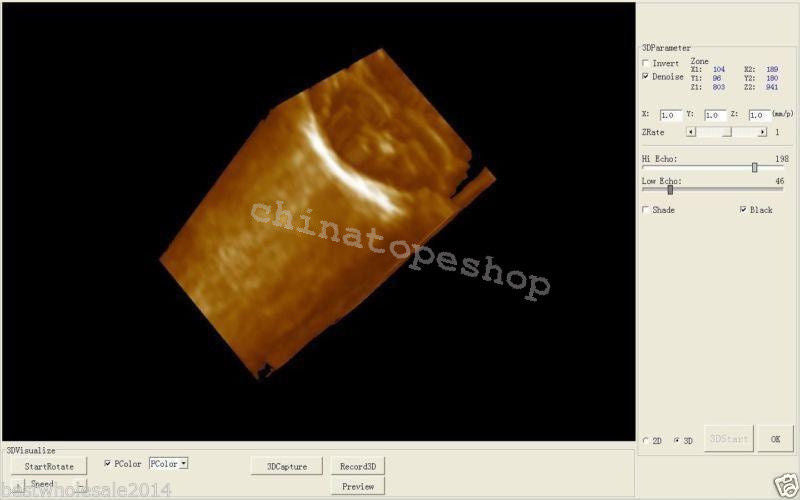

With the inclusion of a 3D workstation, the Laptop Ultrasound Scanner offers enhanced imaging capabilities that allow healthcare professionals to view detailed 3D images. This functionality improves diagnostic accuracy and helps in monitoring various conditions over time. Additionally, the software included enables efficient storage and easy retrieval of images, supporting medical professionals in their evaluations. Hence, this scanner not only provides high-quality imaging but also practical functionalities that are essential for modern medical practices.